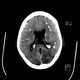

Primary familial brain calcification (PFBC), also known as familial idiopathic basal ganglia calcification (FIBGC) and Fahr's disease, is a rare, genetically dominant, inherited neurological disorder characterized by abnormal deposits of calcium in areas of the brain that control movement. Through the use of CT scans, calcifications are seen primarily in the basal ganglia and in other areas such as the cerebral cortex. [Source: Wikipedia ]